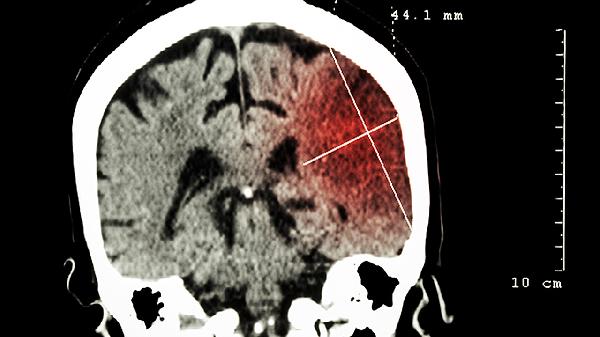

像重症肺炎这样的基础疾病可能导致大脑供氧不足。如果血氧饱和度低于90%,并且持续超过6小时,就可能对脑细胞造成不可逆的损害,因此需要密切监测呼吸频率和血氧水平。

在高烧期间,建议每天摄入至少2000毫升的水分,可以选择含有电解质的饮料或者淡盐水。使用温水擦浴进行物理降温时,避免使用酒精擦拭。当体温超过38.5度时,可以考虑服用对乙酰氨基酚等退烧药物,但一定要按照医生的指导控制用药间隔。在康复阶段,应注重摄入优质蛋白和维生素B族,如鸡蛋、深海鱼和全谷物等,同时避免过度用脑。如果出现嗜睡、抽搐或认知能力异常等情况,应及时进行头部CT检查或腰椎穿刺等进一步诊断。